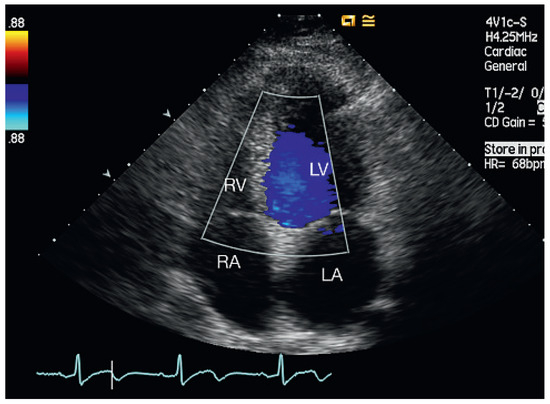

Muscular Ventricular Septal Defect After Mitral and Aortic Valve Replacement

by Augusto Aragão, Dorothea Vogel and Christoph Schmidt

Cardiovasc. Med. 2010, 13(5), 167; https://doi.org/10.4414/cvm.2010.01500 - 26 May 2010

We describe a case series of five patients who were referred to our cardiac rehabilitation department after mitral or aortic valve replacement, and whose transthoracic echocardiographic studies showed postoperative muscular septal defects. Full article

Show Figures

Figure 1